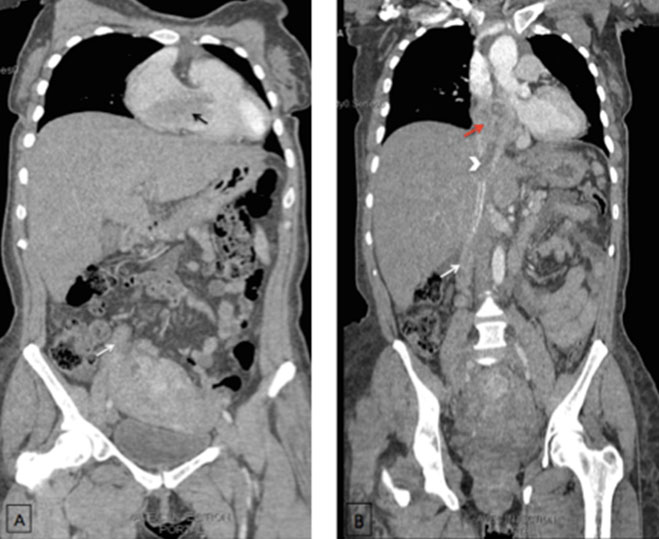

A 59-year-old woman, G0P0 diagnosed with an endometrial carcinoma FIGO stage III in good general condition. The patient underwent a contrast-enhanced abdominal CT showing an expanded right ovarian vein low-attenuation intraluminal material (Figure 1) presumably representing the thrombus. The thrombosis was reaching the inferior vena cava (IVC) and extending to the right atrium and ventricle (Figure 2). Diagnosis of venous thrombosis was highly suspected on the CT based on three criteria: venous enlargement, low-density intraluminal material, and a sharply defined enhancing wall.

Figure 2: Coronal contrast-enhanced computed tomography of the chest-abdomen and pelvic (A) and coronal MIP reconstruction (B) demonstrating a tubular structure (white arrows) extending from the right hemipelvis to the infrarenal inferior vena cava (head arrow) and reaching the right atrium (red arrow) and ventricle (black arrow). It shows enhancing walls and low-attenuation thrombus within it. Note that the uterus is enlarged and heterogeneous.